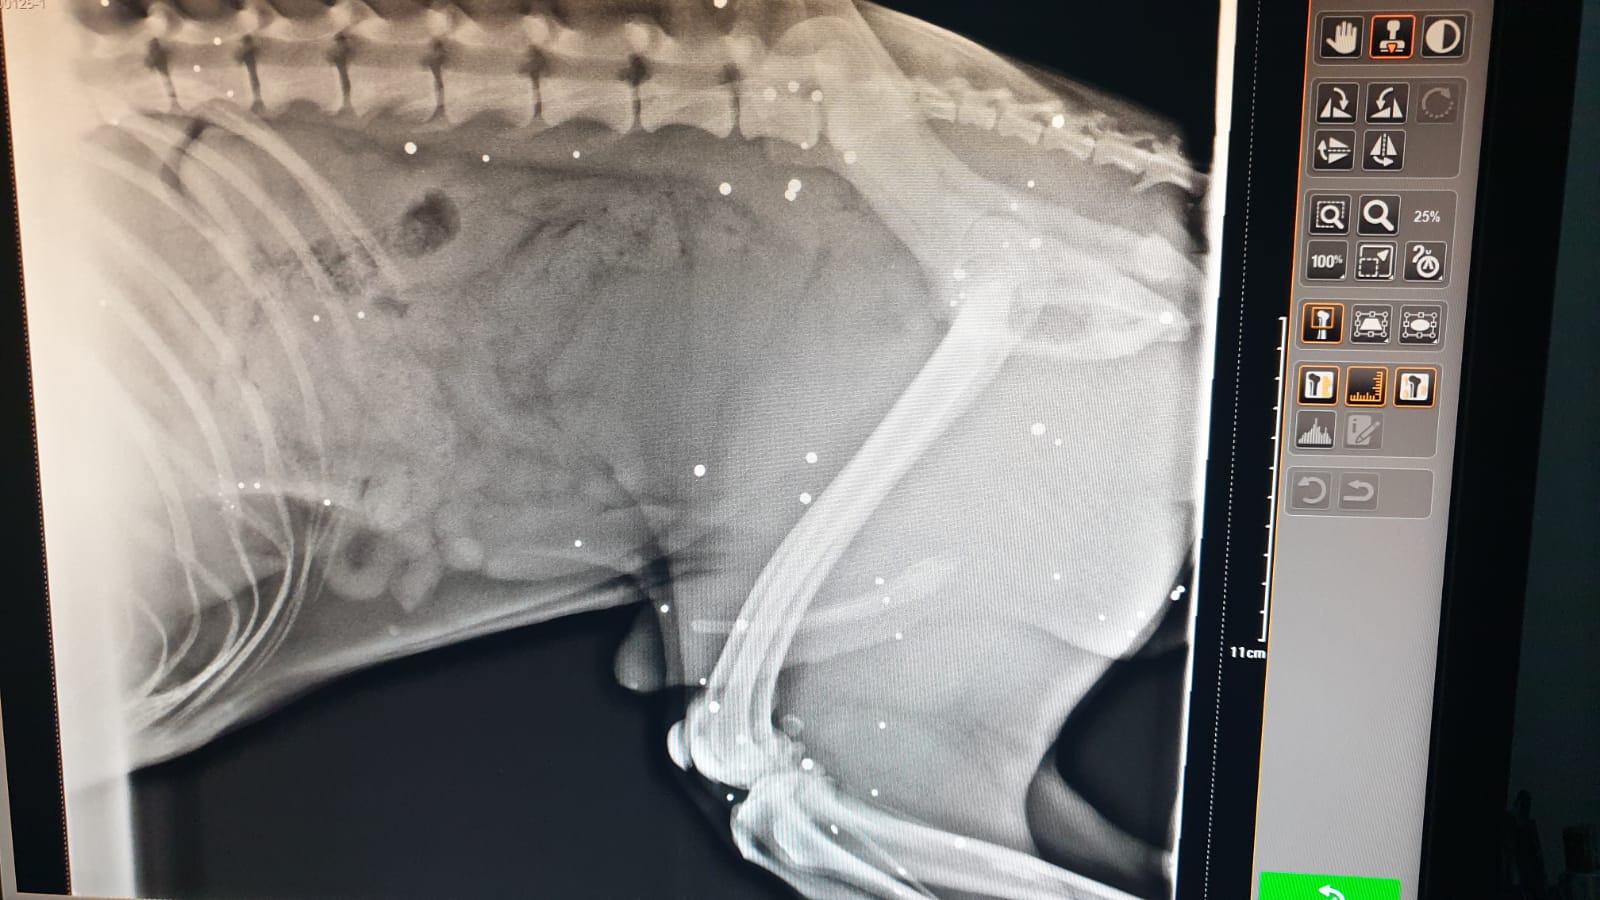

După cum se poate vedea și pe radiografie, în corpul câinelui a rămas foarte mult plumb. „Câinele are foarte mult plumb în el. Medicul veterinar spune că nu a mai văzut niciodată atâtea alice, într-un singur animal. Nu se poate opera momentan, pentru că i-ar face mai mult rău”, ne-au transmis reprezentanții Asociației Rin Tin Tin din Sânnicolau Mare.

Conform medicului veterinar, câinele în vârstă de aproximativ doi ani a suferit, după ce a fost împușcat, plăgi multiple de dimensiuni reduse pe toată suprafața de pe partea stângă a corpului. Alicele de plumb au diametrul 1-3 mm., fiind distribuite haotic în tot corpul.

Acum, într-o variantă fericită, câinele ar urma să trăiască cu plumbul în corp, toată viața sa. Asta dacă nu va face intoxicație… Mai mult, patrupedul poate rămâne cu dureri din pricina alicelor de plumb care au ajuns aproape de oase.

Din cate pot vedea pe radiografie l-a impuscat din fata. Probabil bietul om a vazut cainele cum vine furios spre el si s-a aparat. Sau pur si simplu a vrut sa previna o tragedie.

Mai uită-te odată la radiografie! A fost împușcat din lateral stânga… Dacă era împușcat din față avea tot capul plin nu doar o parte.